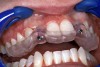

Periapical radiographs were taken to help determine the mesial-distal inclinations of the adjacent tooth roots (Figure 1). The radiographs revealed a serious issue, convergent roots for the right canine and right central, which eliminated that area as a potential implant-receptor site. The space between the left central and canine teeth was minimal, although the roots were relatively parallel. Clinical examination (manual palpation of the root eminences superiorly to the vestibule on the right side) confirmed the root convergence (Figure 2A). The flat, wide zone of the keratinized tissue and lack of interdental papilla was evident for the missing right lateral incisor. There was a marked difference in clinical appearance for the left lateral, which could impact the eventual plan of treatment (Figure 2B). Other significant clinical findings included bilateral facial bone concavities, which existed as a result of the congenitally missing tooth roots. As a diagnostic cue to the underlying bone topography, it is important to follow the demarcation between attached and unattached gingival tissue, and note the crestal width of the available keratinized tissue (Figure 2C).

Figure 2a  Pretreatment buccal views showed (A) root convergence, (B) a difference in clinical appearance of the left lateral, and (C) significant crestal width of keratinized tissue.

Figure 2a

Figure 2b  Pretreatment buccal views showed (A) root convergence, (B) a difference in clinical appearance of the left lateral, and (C) significant crestal width of keratinized tissue.

Figure 2b

Figure 2c  Pretreatment buccal views showed (A) root convergence, (B) a difference in clinical appearance of the left lateral, and (C) significant crestal width of keratinized tissue.

Figure 2c